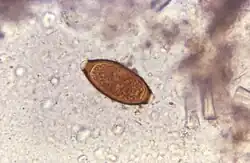

Trichuris trichiura egg

Adult worms are usually 3–5 centimetres (1.2–2.0 in) long, with females being larger than males as is typical of nematodes. The thin, clear majority of the body (the anterior, whip-like end) is the esophagus, and it is the end that the worm threads into the mucosa of the colon. The widened, pinkish-gray region of the body is the posterior, and it is the end that contains the parasite's intestines and reproductive organs. T. trichiura eggs are prolate spheroids, the shape of the balls used in Rugby and Gridiron football. They are about 50–54 μm (0.0020–0.0021 in) long and have polar plugs (also known as refractile prominences) at each end.

Trichuriasis can be diagnosed when T. trichiura eggs are detected in stool examination. Eggs will appear barrel-shaped and unembryonated, having bipolar plugs and a smooth shell.[21] Rectal prolapse can be diagnosed easily using defecating proctogram and is one of many methods for imaging the parasitic infection. Sigmoidoscopies show characteristic white bodies of adult worms hanging from inflamed mucosa ("coconut cake rectum").[22]